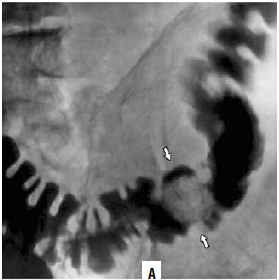

Основным методом рентгенологического исследования толстой кишки является ирригоскопия (рис. 182). Метод заключается в ретроградном введении контрастного вещества через прямую кишку с помощью аппарата Боброва, что позволяет добиться тугого наполнения органа и подробно изучить положение, форму, размеры и особенности контура толстой кишки.

Рис. 182. Рентгенологическая картина рака ободочной кишки (ирригограммы). А – стрелками указан дефект наполнения;

Б – стрелками указан участок циркулярного сужения просвета кишки

При этом также используют метод двойного контрастирования, то есть второй этап ирригоскопии. Второй этап выполняется после опорожнения кишки от рентгеноконтрастной взвеси. Исследование проводят при дозированном заполнении кишки воздухом, используя аппарат Боброва. На фоне двойного контрастирования становится возможным детальное изучение рельефа слизистой оболочки. Интерпретация рентгенологической картины основана на тех же принципах, что и анализ результатов рентгенологического исследования пищевода, желудка и двенадцатиперстной кишки с применением перорального контрастирования. При раке ободочной кишки выявляют участки сужения толстой кишки, определяют «ниши», дефекты наполнения, изменения рельефа слизистой оболочки и оценивают двигательную активность кишки.

Наиболее характерными рентгенологическими признаками рака толстой кишки является наличие:

1) дефекта наполнения (краевого, циркулярного или центрального);

2) ограниченного сужения кишки, сопровождающегося ее расширением выше и ниже пораженного опухолью сегмента;

Эндоскопическая картина 3) неровности контура кишки, атипичного рельефа слизистой, обрыва складок и отсутствие гаустр в области поражения;

4) ригидности стенок кишки;

5) неполной эвакуации контрастного вещества из кишки после ее опорожнения и сохранения стойкого депо бария в области дефекта наполнения.